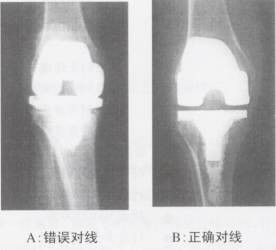

02在病理情況下,由於膝關節的內/外翻,正常的脛股角將發生變化,而下肢的機械軸將不可能通過膝關節的中心,這正是我們在膝關節置換術的術前計畫和手術中需要通過測量和截骨解決的問題。通過計算和測量準確的截骨才能使下肢力線獲得正確的重建。下肢力線的重建是確保手術成功的關鍵,也是避免術後因應力不均而造成鬆動的重要環節。

關節線(jointline)是膝關節對線的另一重要內容。在冠狀面的關節線升高和降低將影響到髕骨和滑車的相對位置,導致高位或低位髕骨。因此,TKA手術中重建關節線的正常高度也是TKA手術中的重要環節(圖示)。一般來說,關節線的降低比關節線的升高更有害。另一方面,解剖上的脛骨關節線在矢狀面上雖有一定的後傾角度,但如果考慮到半月板的因素,事實上脛骨關節面的後傾幾乎為零。儘管許多膝關節假體強調脛骨的後傾,但已有足夠的證據表面,脛骨後傾並無十分必要。